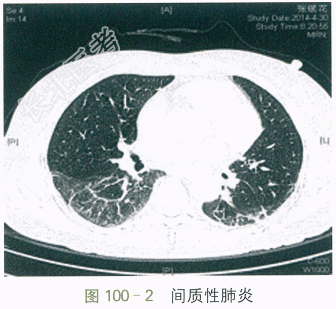

患者,女性,59岁。因“口干眼干5年,伴胸闷气促2个月”入院。患者5年前起出现口干,进食干性食物时需饮水方可咽下,伴有双眼干涩、泪少,未予特别重视,3年前出现牙齿逐渐变黑,继而小片状脱落(见图100-1)。2个月前出现咳嗽、咳白痰,至当地医院治疗后一过性好转,但不久即出现活动后胸闷气促,上两层楼即感明显胸闷气促、呼吸困难,休息后稍好转,同时伴四肢及双手掌指关节酸痛。近日胸闷气促加重,休息状态下亦感胸闷。病程中无头晕头痛、无畏寒发热、无雷诺现象、无皮疹及光敏、无关节晨僵、无反复腮腺肿大。患者神志清,精神可,食纳夜眠可,二便正常,体重无明显减轻。高血压史14年,自服珍菊降压片1片bid,平素血压控制在120mmHg/80mmHg左右。否认糖尿病,冠心病史。否认病毒性肝炎及结核病史。否认药物过敏史。体格检查:T37℃,P76次/min,R18次/min,BP120mmHg/80mmHg。全身浅表淋巴结未及肿大,无皮疹及皮下结节。口腔可见多发龋齿,舌面光滑。两下肺可及Velcro啰音,心界不大,各心脏瓣膜区未及杂音。腹平软,肝脾肋下未及,双下肢无水肿。四肢各关节未及肿胀,压痛(-)。自身抗体:抗核抗体1:320,抗SSA抗体阳性,抗SSB抗体阳性,抗线粒体抗体阳性,抗ds-DNA抗体15.4IU/ml,抗核小体抗体2.0RU/ml。免疫球蛋白:IgG20.29g/L,IgA4.66g/L,IgM1.13g/L,IgE211.0IU/ml。血常规:RBC 4.75×10¹²/L,Hb 130g/L,WBC 7.06×10⁹/L,PLT 298×10⁹/L;ESR51mm/h;hs-CRP7.6mg/L。补体:C31.33g/L,C40.23g/L。血气分析:pH7.45,PaCO₂38.0mmHg,PaO₂65.0mmHg,SaO₂93.0%;乙肝免疫标志物、丙肝抗体、HIV抗体全阴性。肺HRCT:两肺间质性炎症(见图100-2)。腹部B超:肝脂肪浸润。心超:未见异常。肺功能:中度限制性通气功能障碍。